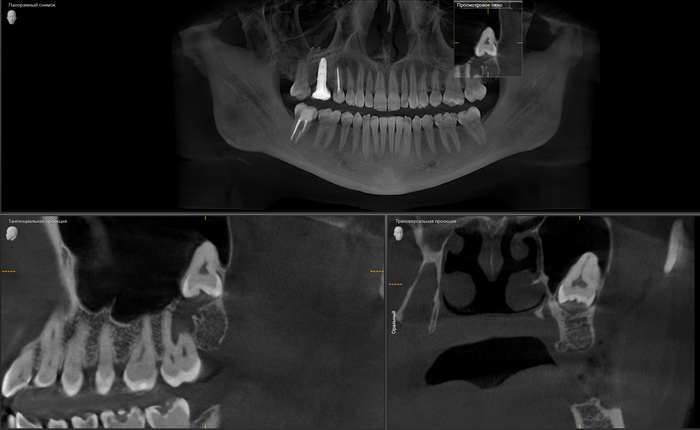

Вжух и год позади:

В целом, каких-то явных изменений нет. В подтверждение тому, что это не один и тот же снимок, вы можете обратить внимание, что на имплантате уже установлена постоянная коронка.

Добрый вечер… А что это значит?... Прекрасно видно, что фолликулярная киста начала расти и оттеснять зуб мудрости дальше в пазуху, что несколько затрудняет его удаление. Блять, подумал я, надо было сразу удалять.